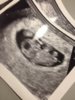

Meillä jaettiin vielä ainakin syksyllä. Mulla ihan sama, että tykkäsin esikoisesta kirjoitella sinne. Syksyllä kieltäydyin opuksesta, kun ajattelin, että laitan vaikka eri värillä toisen raskauden jutut. Vertailut olis samoissa kansissa. Syksyinen raskaus meni vaan kesken ja oonkin nyt miettinyt, että ottaisko sen verran taikauskoa peliin mukaan ja ottais oman opuksen tälle raskaudelle.

. Ja itselleni tuli nyt jotenkin luottavainen olo, että eiköhän se nyt tästä. Toivotaan, että olo on oikea :)